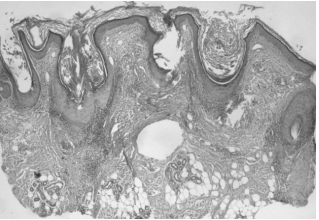

Первичные высыпания фолликулярного красного плоского лишая гистологически представлены в виде перифолликулярного лимфоцитарного инфильтрата на уровне фолликулярной воронки и перешейка наряду с вакуольной альтерацией клеток наружного волосяного влагалища и клиновидным гипергранулезом в устье пораженного волоса. В более длительно существующих случаях визуализируются перифолликулярный фиброз и атрофия эпителия на уровне фолликулярной воронки и перешейка, что представлено в характерной конфигурации «песочные часы». При длительно существующих случаях на месте алопеции определяются вертикально ориентированные эластические волокна, которые заменяют разрушенные волосяные фолликулы.

Аналогичную гистологическую картину мы получили и в нашем случае. Это терминальная стадия рубцовой алопеции без волосяных фолликулов, что позволяет поставить диагноз «псевдопеллада Брока» [13] (рис. 6–10).

Рис. 6. Лимфогистиоцитарные инфильтраты вокруг волосяных фолликулов в их истмической зоне с их атрофией в виде «песочных часов» (слева). Рубцовая атрофия (справа) с полным исчезновением волосяных фолликулов и сальных желез. Мышцы, поднимающие волос, сохранены. Окраска гематоксилином и эозином, ув. ×40

Рис. 7. Тот же препарат, левая часть, ув. ×100

Рис. 8. Тот же препарат, правая часть, ув. ×100